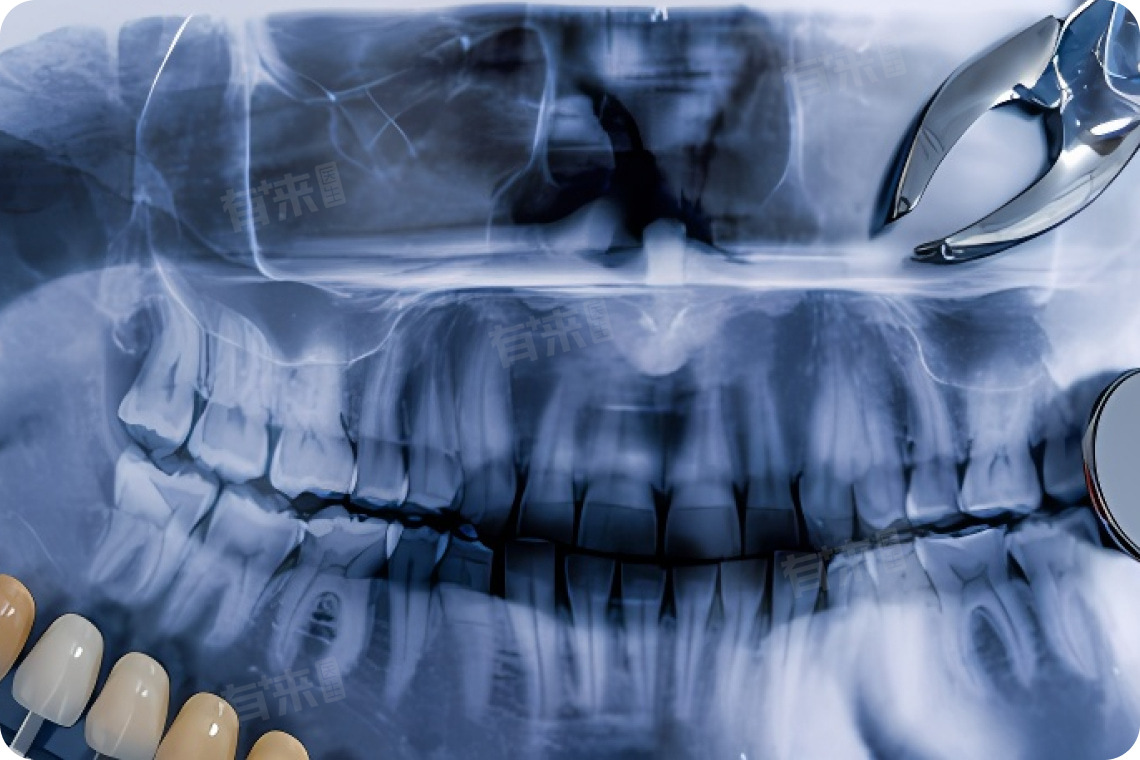

种牙相关注意事项主要包括口腔卫生、饮食调整、生活习惯等,以促进伤口的愈合和种植牙的成功。种牙并非适合所有情况,也存在一些禁忌症,主要体现在年龄因素、健康状况等方面。

- 口腔局部条件:患有严重牙周炎、牙槽骨严重吸收、缺牙区间隙不足等口腔疾病者,不宜进行种植牙手术。口腔颌面部有良恶性肿瘤、颌骨病变、骨质疏松、骨软化症和骨硬化症等,也不适合进行种植牙手术。